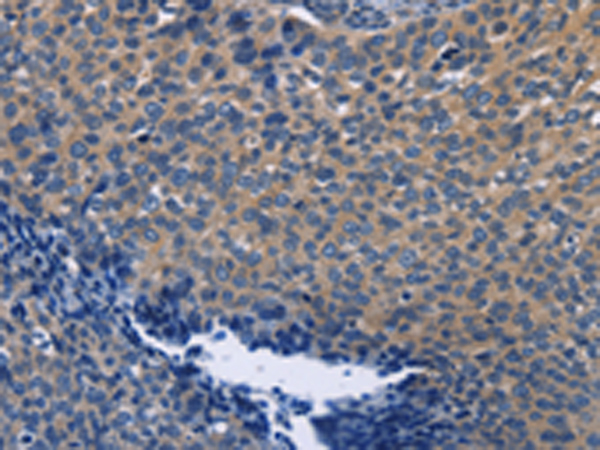

分类: 科研抗体货号: P00648别名: PHD3; HIFPH3; HIFP4H3应用: IHC反应种属: Human, Mouse, Rat